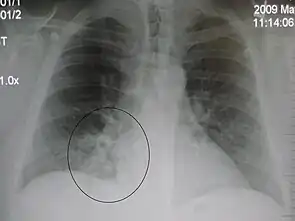

| A chest X-ray showing a very prominent wedge-shape bacterial pneumonia in the right lung | |

- Normal AP CXR

Normal lateral CXR

AP CXR showing left lower lobe pneumonia associated with a small left sided pleural effusion

AP CXR showing right lower lobe pneumonia

AP CXR showing pneumonia of the lingula of the left lung

Right upper lobe pneumonia as marked by the circle.- Left upper lobe pneumonia with a small pleural effusion.

- Right lower lobe pneumonia as seen on a lateral CXR